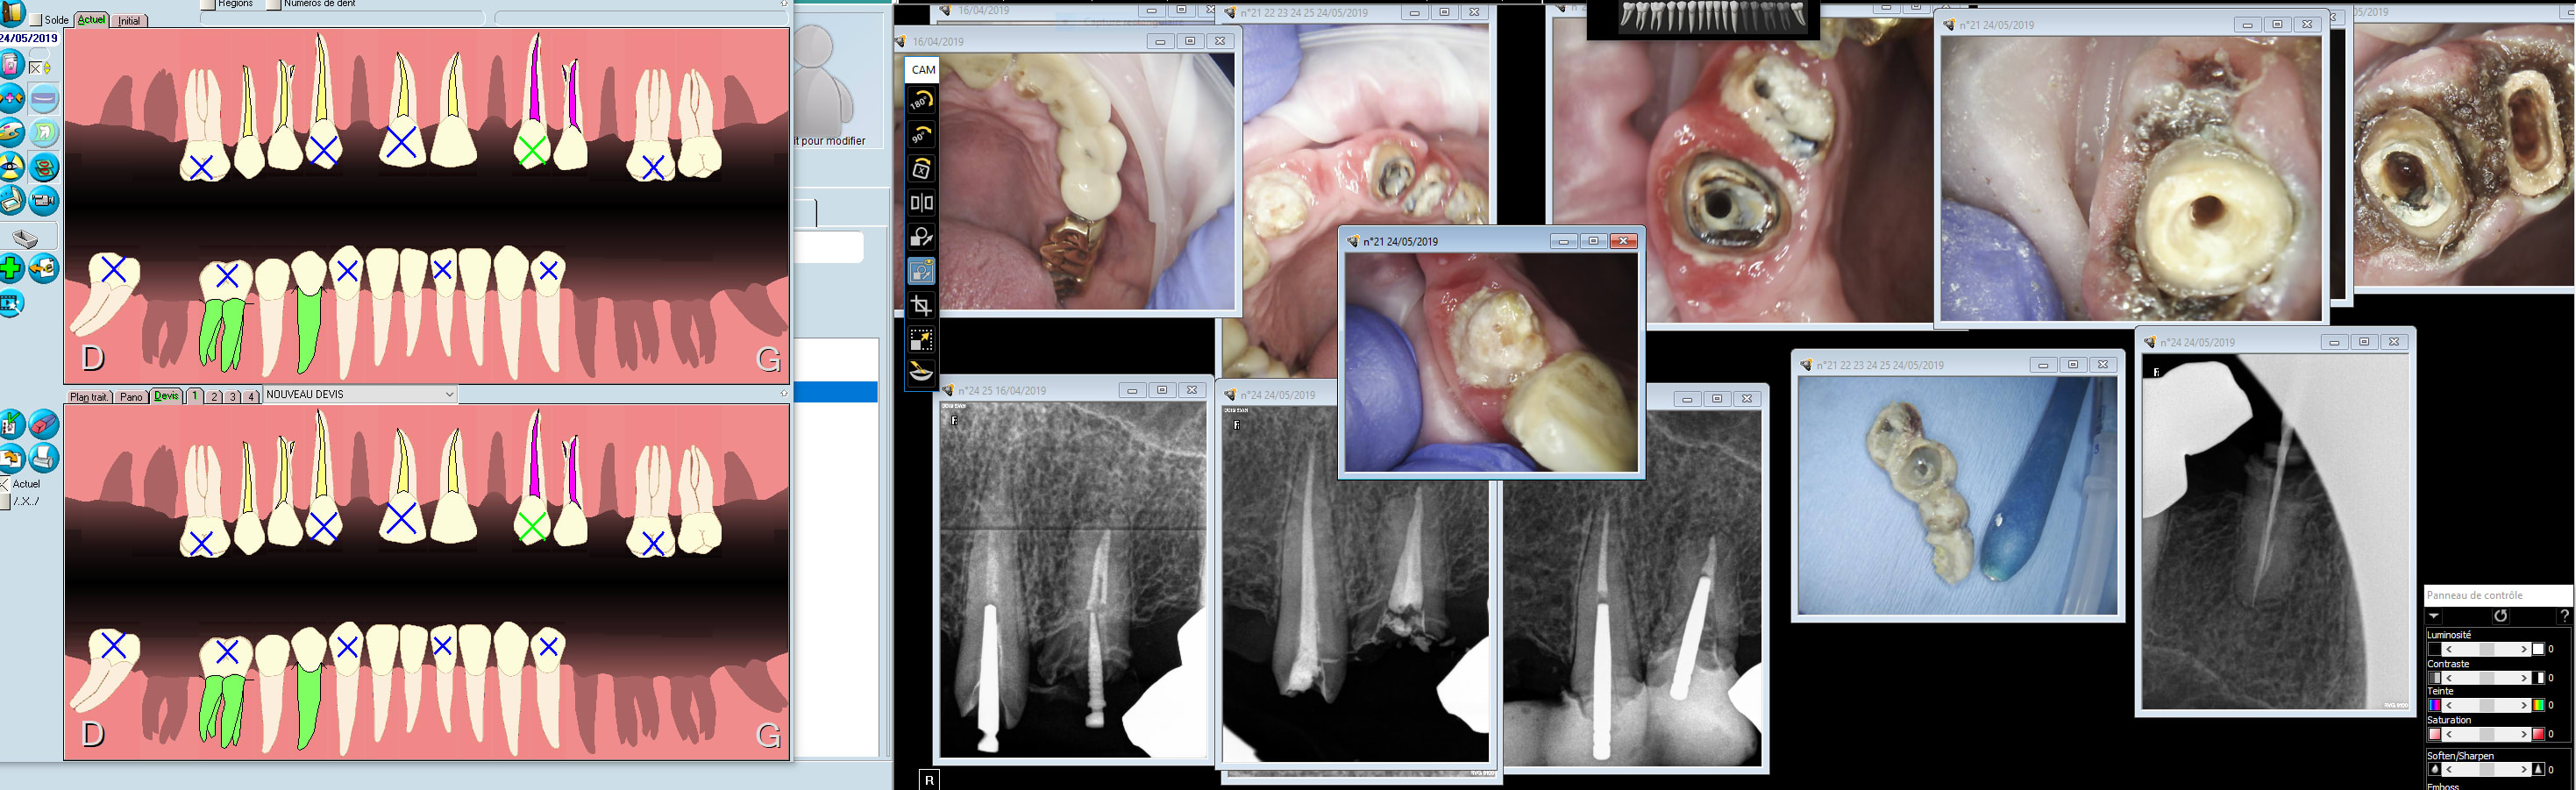

Tu sais les commentaires ça ne vaut pas le choc des images. J'ai réalisé des RTE taille empreinte provisoires , nous n'étions pas dans des conditions idéales.... Tu vois quand je vais ouvrir l'imagerie pour ce patient ces photos vont réapparaitre, ca te rafraîchit la mémoire plus que des commentaires. Comment ça pissait le sang nom de dieu. -))))

4 ans de provisoires en place..... Lui ne recommencera plus ca pète bien sur un 55 pouces. Le poids des mots mais le choc des photos. -)))

Meme dans les cas extrêmes tu peux assurer l'hémostase et faire une empreinte optique. Ic ic demandés + re provisoires par dessus + points sur les i pour l'hygiène.